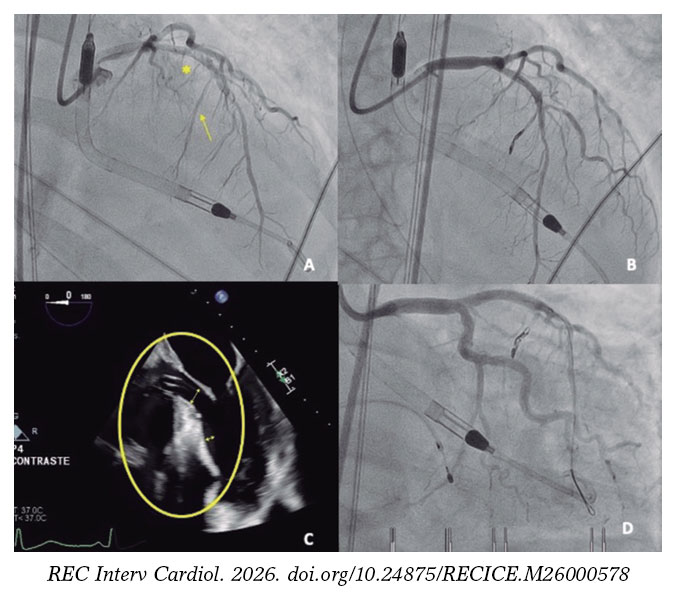

Implantation of the Impella-CP device (figure 1D, asterisk), with flow adjusted to 2.4 L/min (P4) to prevent suction, resulted in immediate hemodynamic and respiratory improvement, as well as a reduction in mitral regurgitation (figure 1E,F; arrows indicate the systolic S wave). A second septal branch (SB) showed extrinsic compression and was selected after confirmation of septal perfusion (figure 2A; arrow indicates second SB; asterisk: first SB). Two coils were deployed (figure 2B) due to potential reversibility, resulting in immediate flow reduction and DLVOTO improvement.

After 24 hours, the patient’s hemodynamic status deteriorated. Due to a slight increase in cardiac enzymes and recurrence of DLVOTO, alcohol ablation of the second SB was performed. Because basal septal contractility persisted (figure 2C, oval), occlusion of the first SB was also undertaken. Due to the impossibility of selective catheterization (figure 2D), a drug-eluting stent was implanted in the proximal left anterior descending coronary artery; thereafter, basal septal akinesia and mild mitral regurgitation were observed (video S2).